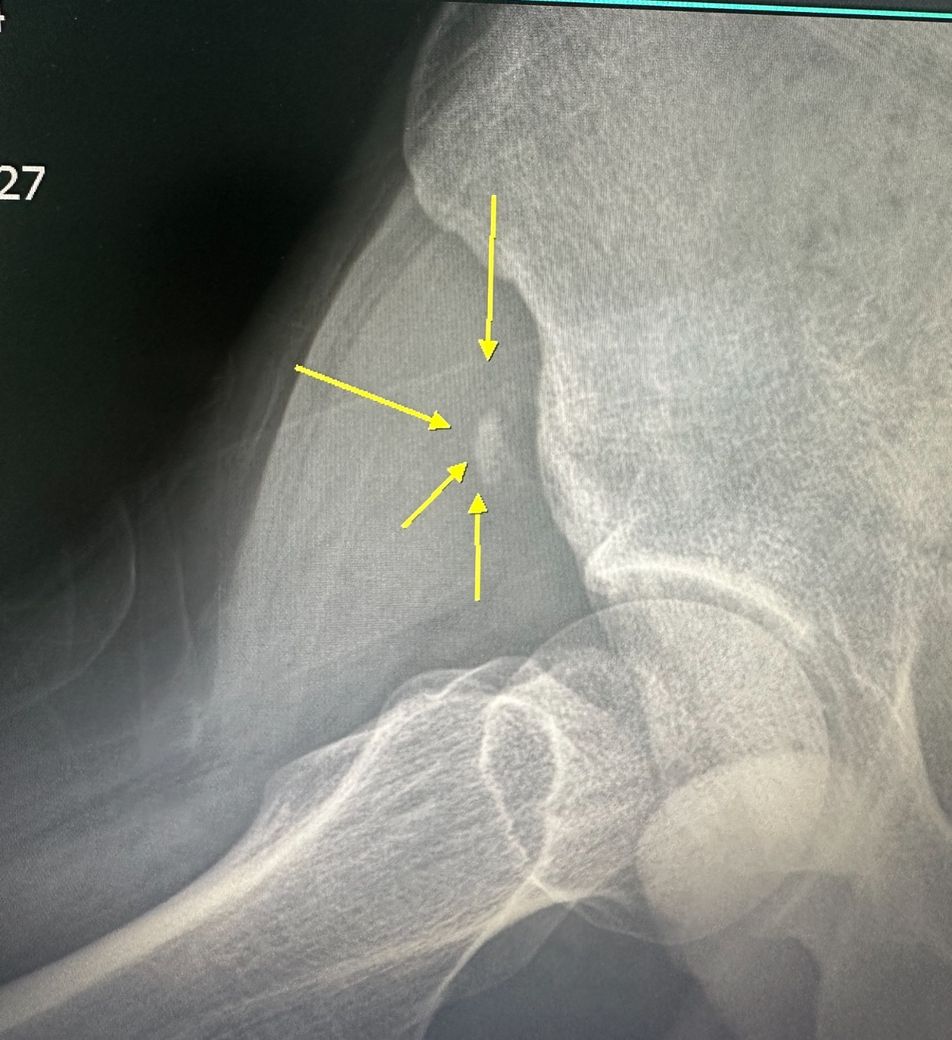

축구하다가 견열골절 부상당했습니다.

1년전 축구하다가 오른쪽 골반쪽에 견열골절 부상을 당했습니다

• 1번 째 사진